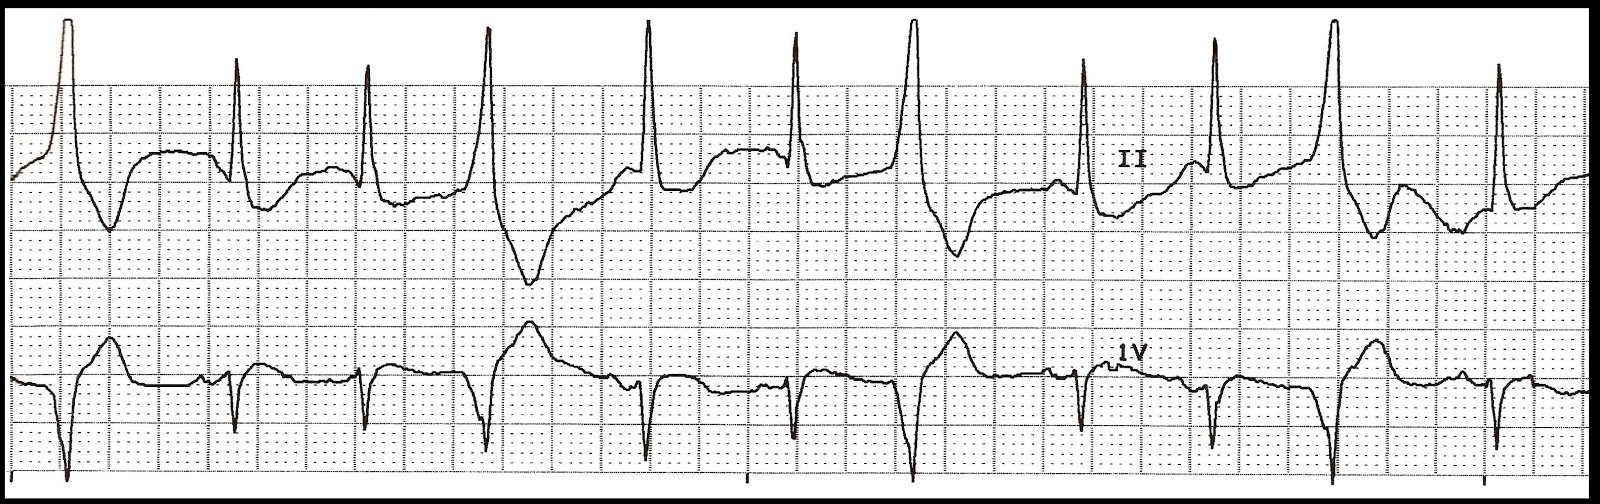

10. Identify the following rhythm.

a. Sinus rhythm with multifocal PVCs

b. Sinus rhythm with trigeminal PVCs

c. Sinus rhythm with unifocal PVCs

d. Sinus rhythm with couplets of PVCs

10. b. Sinus rhythm

with trigeminal PVCs